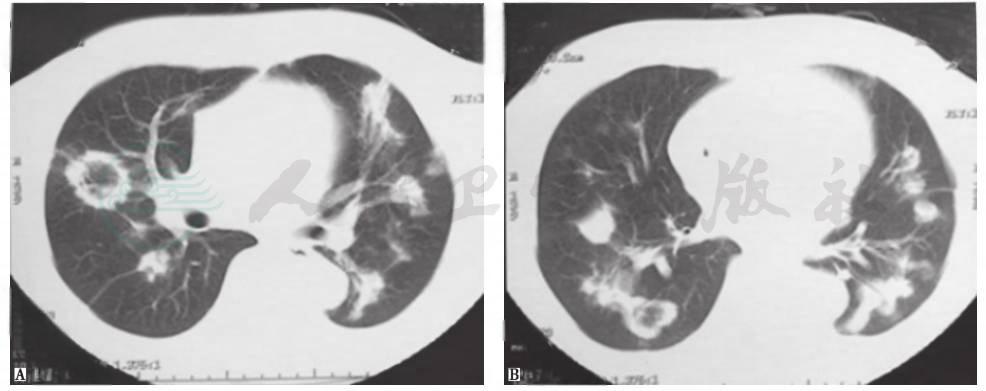

本例患者为老年女性,平时身体健康,无结构性肺病病史,入院前行肠镜检查提示乙状结肠溃疡性浸润性病变,且有明显体重下降表现,不能排除胃肠道肿瘤肺转移的可能。肺转移性肿瘤可分为血行转移和淋巴性转移,以前者多见。经血行转移时可出现双肺结节样病灶,多为圆形或类圆形,边缘光整,密度均匀,以两中下肺多见(图3)。而本例患者胸部CT表现为不规则结节影,部分可见支气管充气征象,且短期进展迅速,考虑为肺转移性肿瘤可能性不大,但须进一步检查相应临床指标以排除之。

图3肺转移性腺癌胸部CT表现

男性患者,58岁,咳嗽、咳痰3个月,气喘2个月,诊断为肺转移性腺癌。胸部CT见双肺多发结节性病变,部分空洞形成

图4侵袭性肺曲霉菌病胸部CT表现

女性患者,35岁,乏力1个月,发热5天,诊断为粒细胞缺乏症合并侵袭性肺曲霉菌病。胸部CT可见双肺多发实变斑片影,多发晕征结节伴新月形空洞形成

图5肺曲霉菌感染胸部CT表现

女性患者,55岁,间断发热1个月,咳嗽1周,痰中带血1天,诊断为侵袭性肺曲霉菌病。胸部CT可见双肺多发结节影伴反晕征形成

图6韦格纳肉芽肿胸部CT表现

女性患者,21岁,间断咳嗽2个月,诊断为韦格纳肉芽肿。胸部CT可见双肺多发结节影伴空洞形成,各结节影与血管关系密切